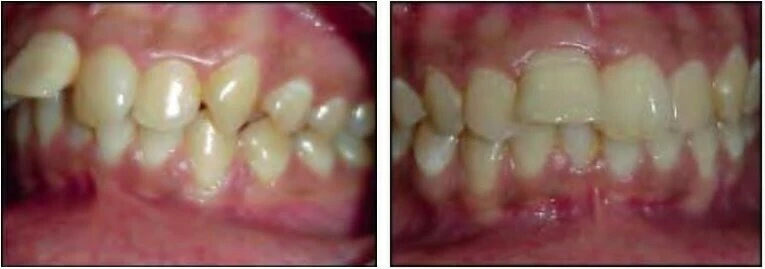

2) KHÔNG CÂN XỨNG GIỮA CÁC CUNG HÀM

Kiểu sai khớp cắn này đặc trưng bởi sự tương quan bất thường giữa các răng và các nhóm răng của một cung hàm với cung hàm còn lại. Tình trạng không cân xứng giữa các cung răng có thể xảy ra theo ba mặt phẳng trong không gian – mặt phẳng đứng dọc, mặt phẳng đứng ngang hoặc mặt phẳng ngang

2.1 SAI KHỚP CẮN THEO MẶT PHẲNG ĐỨNG DỌC

Trường hợp này có thể được chia thành hai phân loại:

Khớp cắn nằm về phía trước so với bình thường

Với loại này, khi các răng gặp nhau tại khớp cắn trung tâm thì cung răng hàm dưới nằm về phía trước hơn.

Khớp cắn nằm về phía sau so với bình thường

Ở đây, khi các răng gặp nhau tại khớp cắn trung tâm thì cung răng hàm dưới nằm về phía sau hơn.